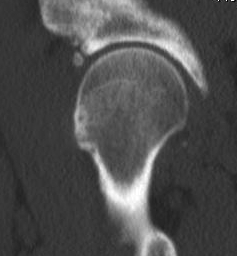

CT

Cam impingement